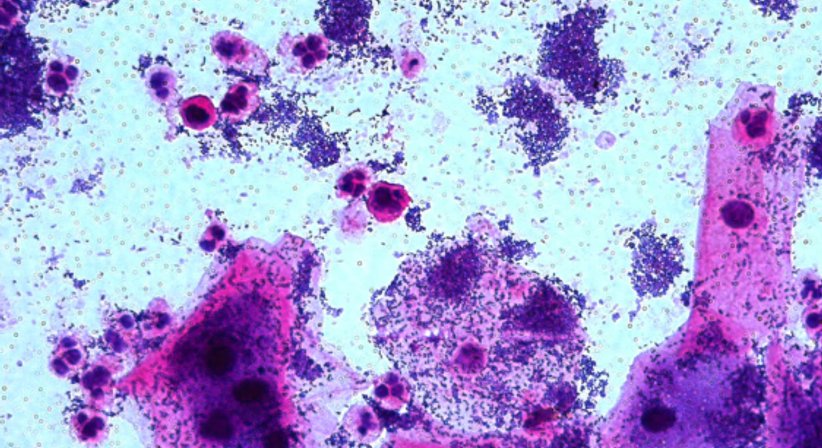

Als „Goldstandard“ für die Differentialdiagnose von vaginalen Infektionen ist die mikroskopische Untersuchung des Abstrichpräparates nach GRAM-Färbung zu bezeichnen. Diese sollte aber nach eindeutigen Kriterien (nach Spiegel oder Nugent) beurteilt werden.